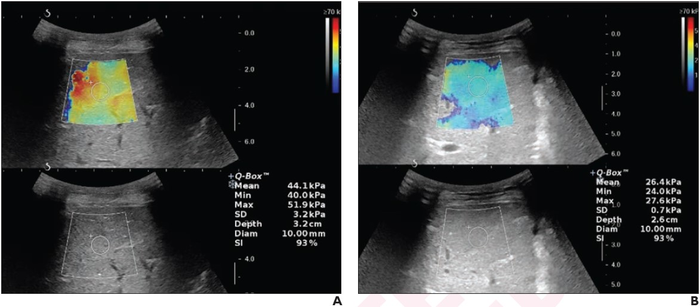

Leesburg, VA, October 1, 2021 According to ARRS’ American Journal of Roentgenology ( AJR ) , liver stiffness measurements (LSM) obtained by 2D shear-wave elastography (SWE) may serve as a useful quantitative adjunct to Color Doppler ultrasound (CDUS) in monitoring children with chronic Budd-Chiari syndrome (BCS) for disease recurrence after percutaneous interventional treatment.

Sharma and team’s prospective study included children with chronic BCS and planned image-guided intervention. CDUS and 2D SWE were performed at baseline; at 24 hours, one month, and three months after intervention; and thereafter every three months or at the time of clinically suspected recurrence.

In the 32 children (28 boys, 4 girls; mean age, 9.0 years) who underwent image-guided intervention for chronic BCS, median LSM was 43.7 kPa at baseline and 22.5 kPa, 18.7 kPa, and 16.7 kPa at 24 hours, one month, and three months, respectively, after intervention. In eight of nine patients with recurrence, LSM was increased, compared with the pre-recurrence measurement.